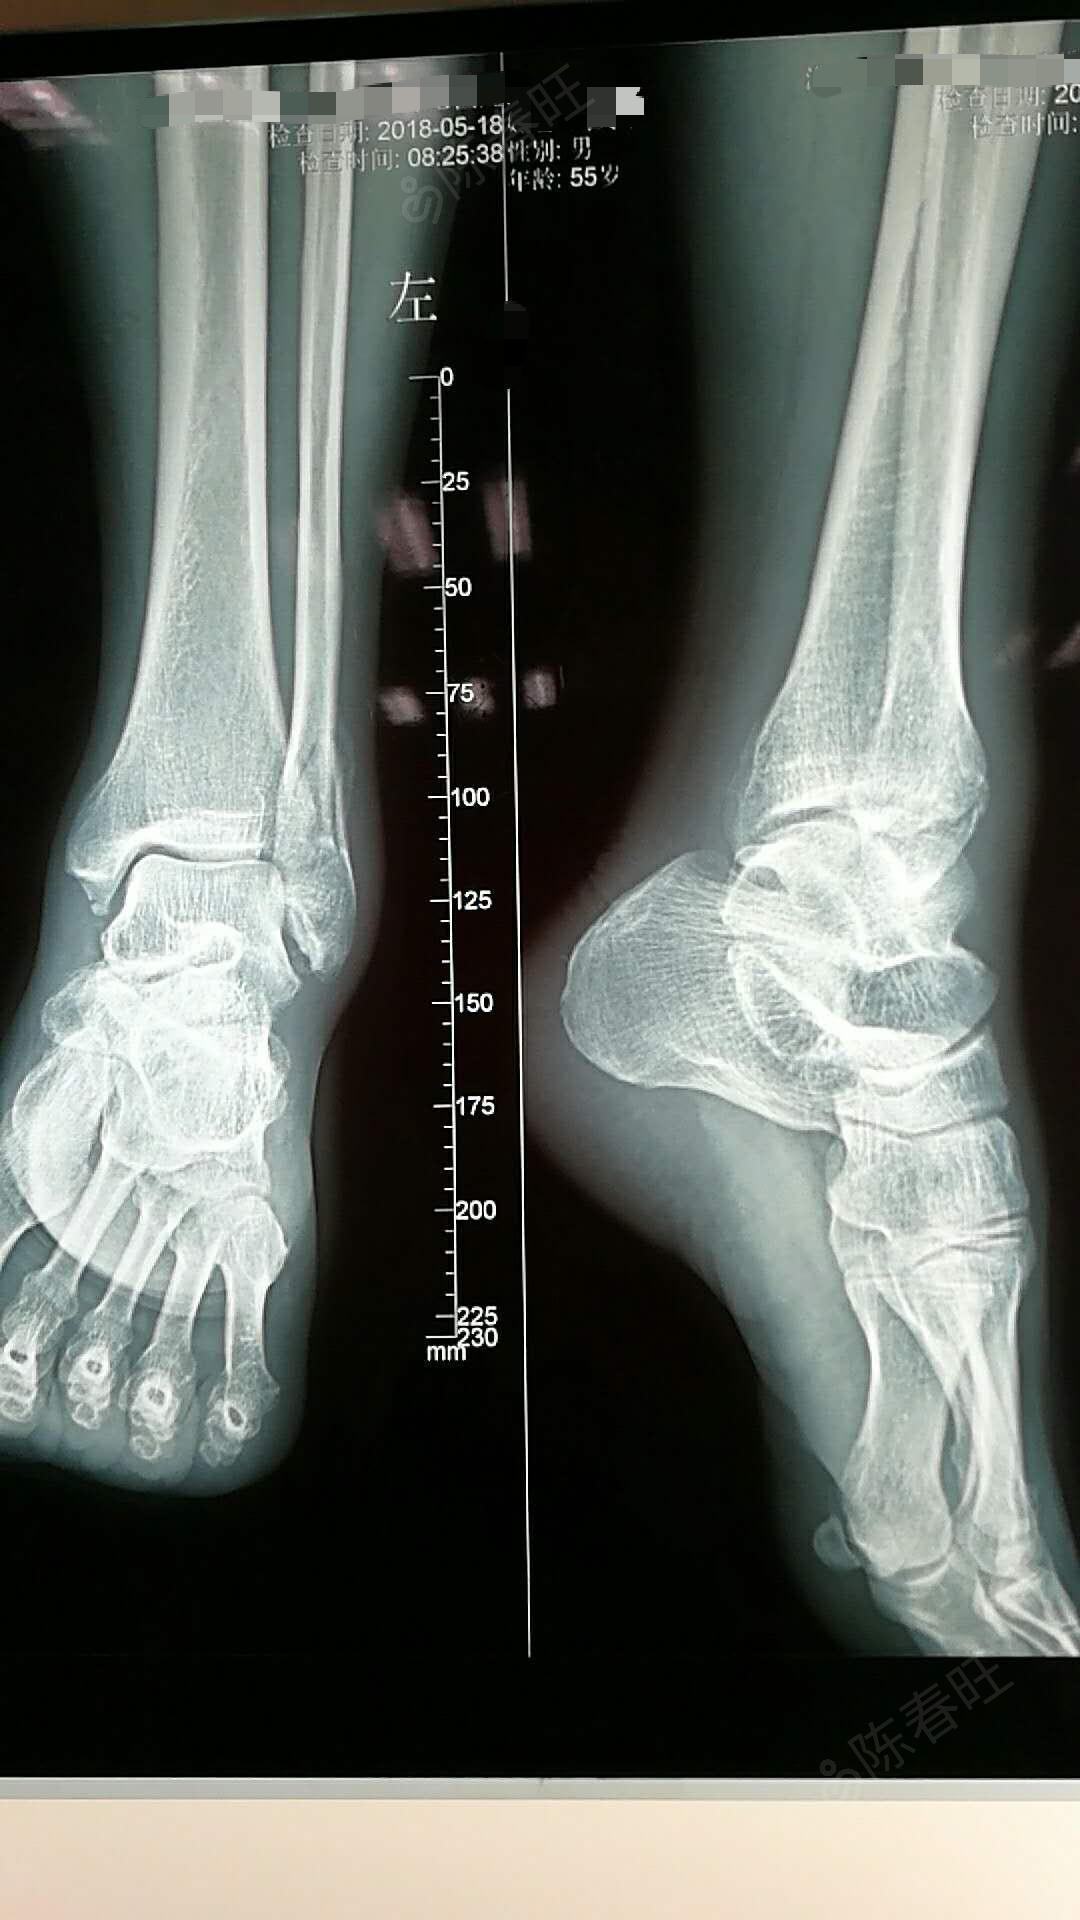

内外踝骨折术前x线片

左内外踝骨折